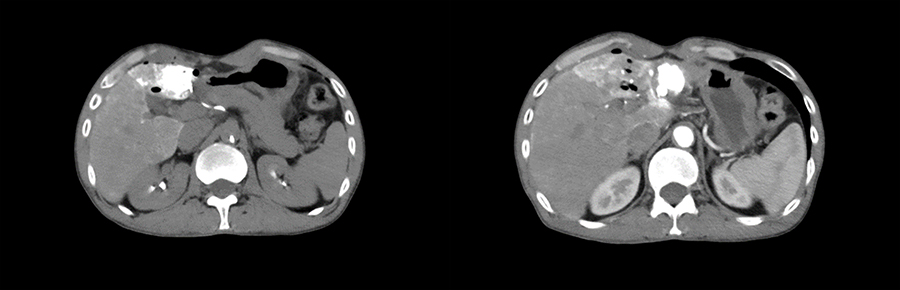

▲ 患者一计划进针路线

▲ 患者二计划进针路线